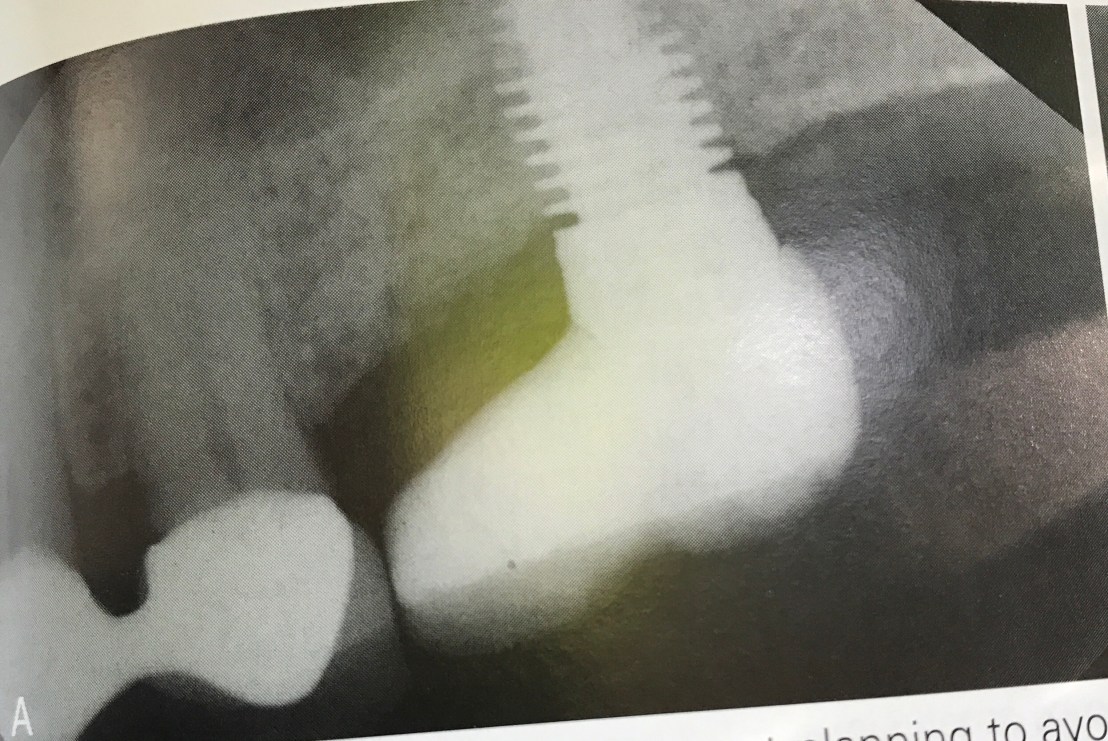

แสดงการ Gain Primary stability โดยการใช้ Osteotome (รูป B คือหลังใช้ Osteotome)

แสดงความผิดพลาดในการวางตำแหน่ง จะเห็นได้ว่า แม้จะมี socket ถอนฟันเป็นตัว guide แต่ตำแหน่งที่ฝังยังออกไป Distal มาก

ดังนั้นการใช้ข้อมูลจาก X-ray + Surgical stent จึงยังเป็นสิ่งจำเป็นอยู่ แม้ในเคส Immediate ก็ตาม